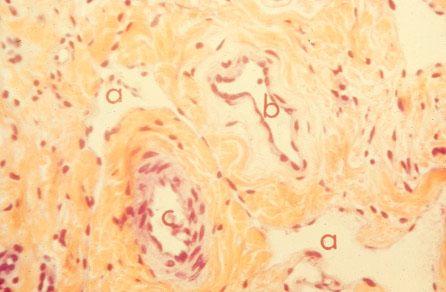

VI-29 (3) Arteriole and Venule. a: lymphatics, b: venule, and c: arteriole.